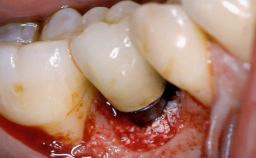

Surgical Management of Peri-Implantitis: Reconstructive Surgical Treatment with Three-Year Follow-up After Treatment

Despite anti-infective surgical treatment, some patients may experience recurrent infection and progressive bone loss requiring additional treatment. Removal of Implant Due to Recurrent Infection describes a conservative approach using an implant retrieval tool without the need for excessive bone removal or use of a trephine.

A 70-year-old female patient was referred by her general dentist to the periodontist for assessment and management of an infection associated with implant 36. The general dentist had noted suppuration on probing during examination.